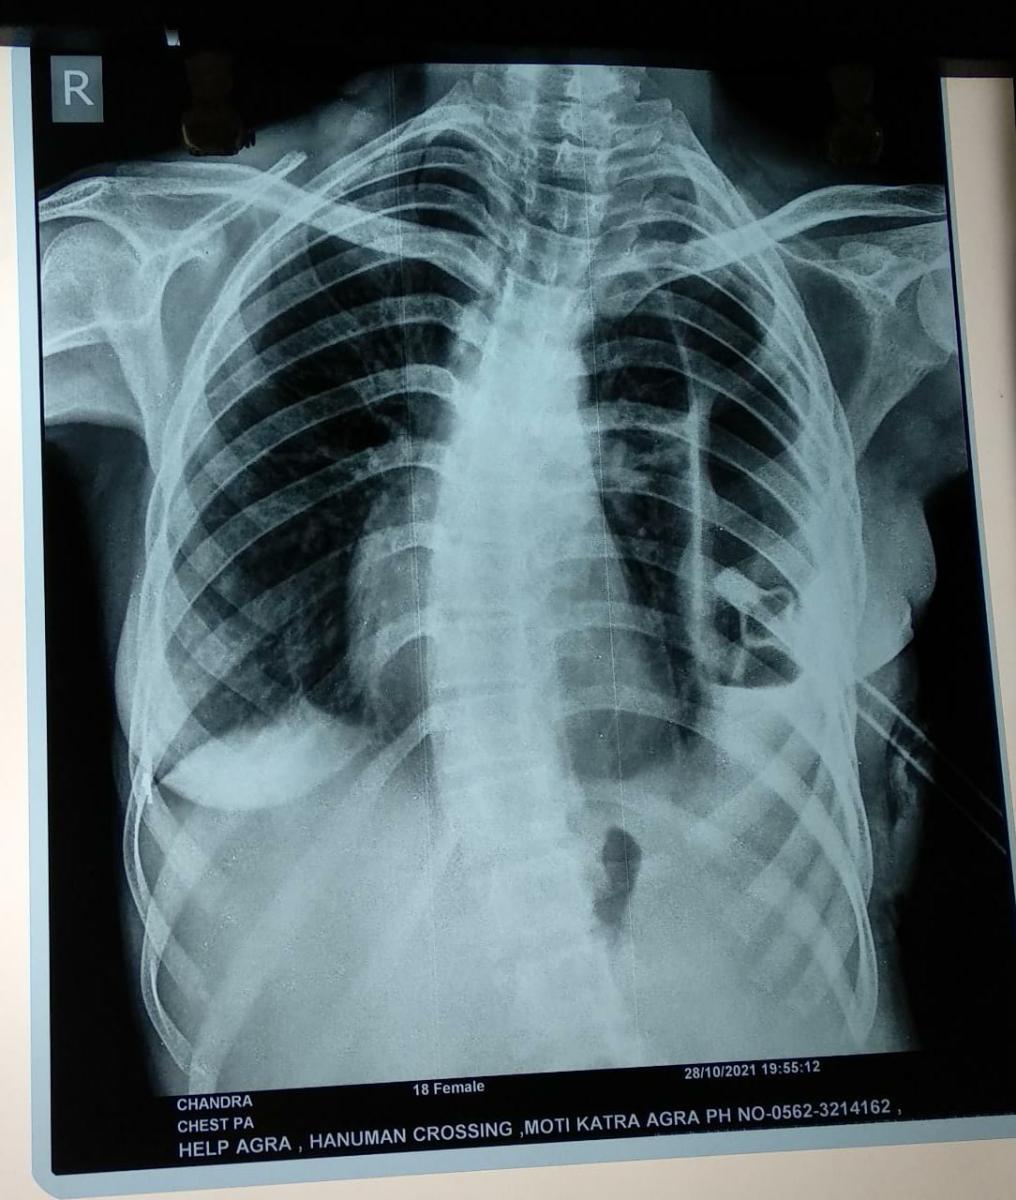

Photo Gallery Dr. Monika Gupta - Photo Gallery 7 5 2 8 6 Dr. Atul Kumar Gupta - Photo Gallery « ‹ of 3 › » Video Gallery